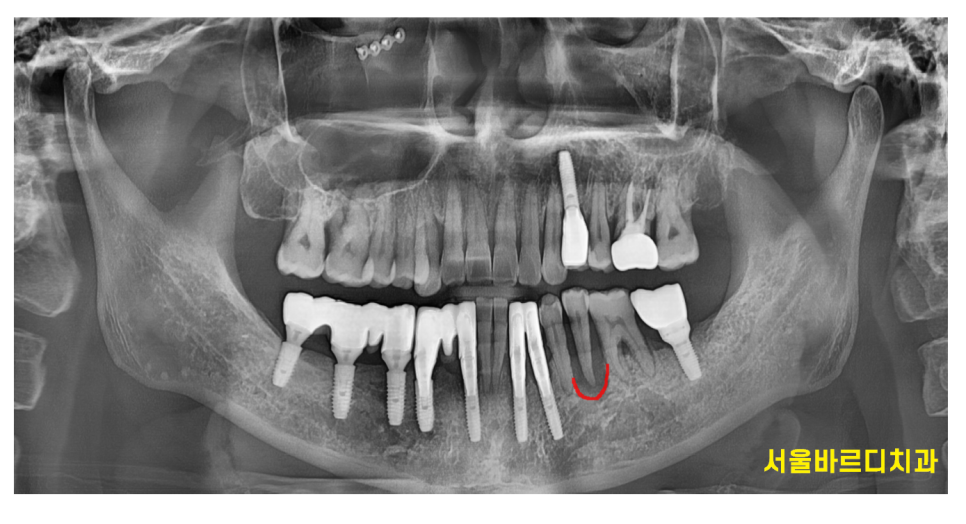

눈으로 잇몸 내부 상태를 확인할 수 없지만

x ray를 통해 알 수 있는데요~

230411

잇몸뼈가 녹았을 경우 텅 빈 공간이 되어버리고

밀도가 낮아져

주변 잇몸뼈에 비해 까맣습니다.

파노라마만 찍어도 확인이 가능하고

ct는 더 정확합니다.

패인것까지 보이거든요.

231103